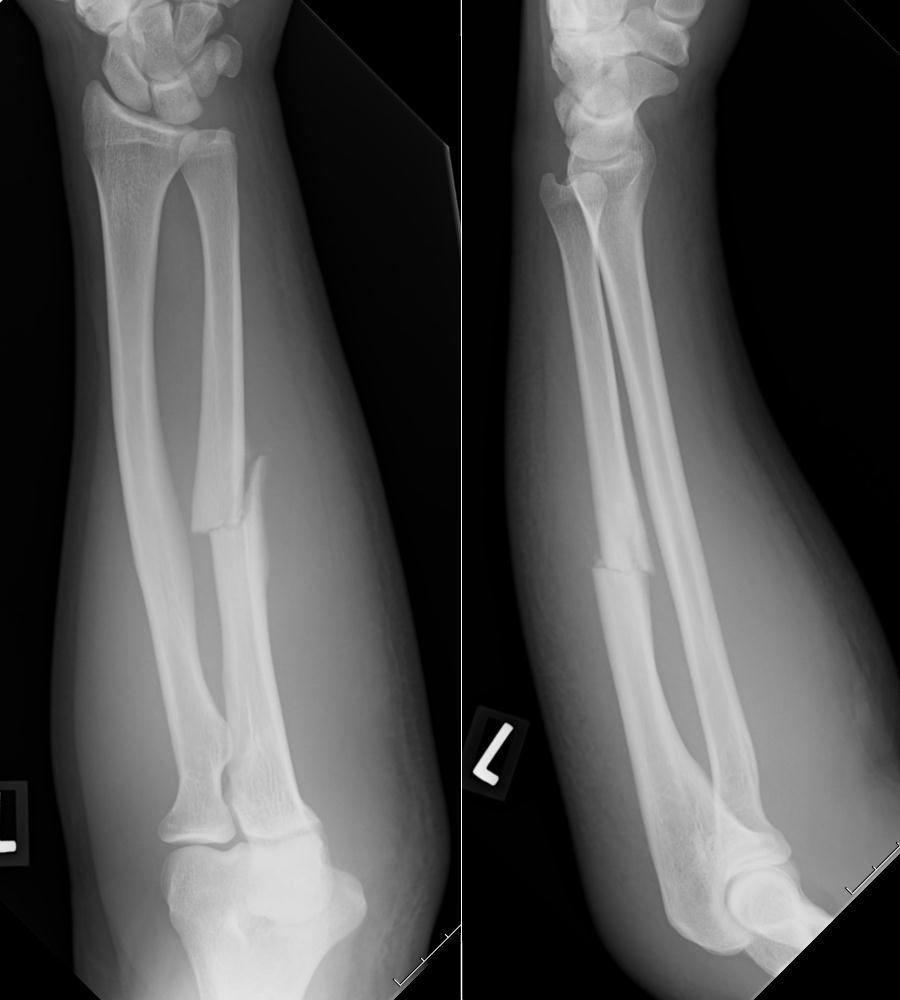

腕の骨折

剪定作業中、高所から転倒負傷されました。